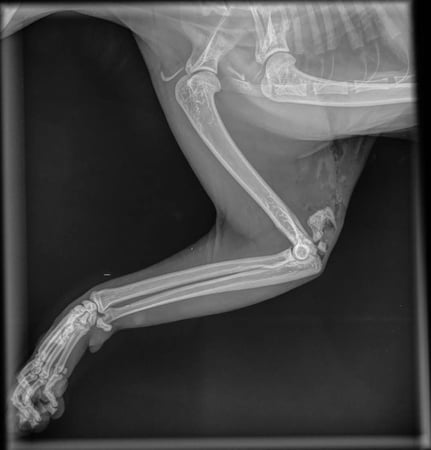

Diagnostica: radiografie, esami del sangue, chirurgia, ecocardio ed ecografia addominale (con specialisti su appuntamento)